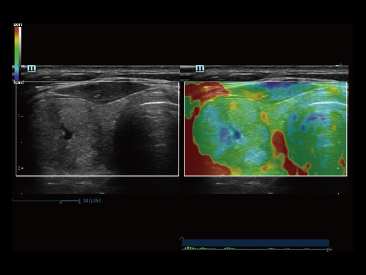

Die St?rken des Resona 7 sind bis ins kleinste Detail durchdacht. Seine erstklassige Bildqualit?t ist das Ergebnis einer erfolgreichen Fusion. Mindray und Zonare Medical Systems haben ihren Kernkompetenzen geb├╝ndelt, um ein Premiumsystem Wirklichkeit werden zu lassen. Dank der Vector Flow-Funktion k?nnen bei Gef??untersuchungen mehr als 400 Bilder pro Sekunde dargestellt werden. Somit entstehen ganz neue M?glichkeiten der Diagnose.